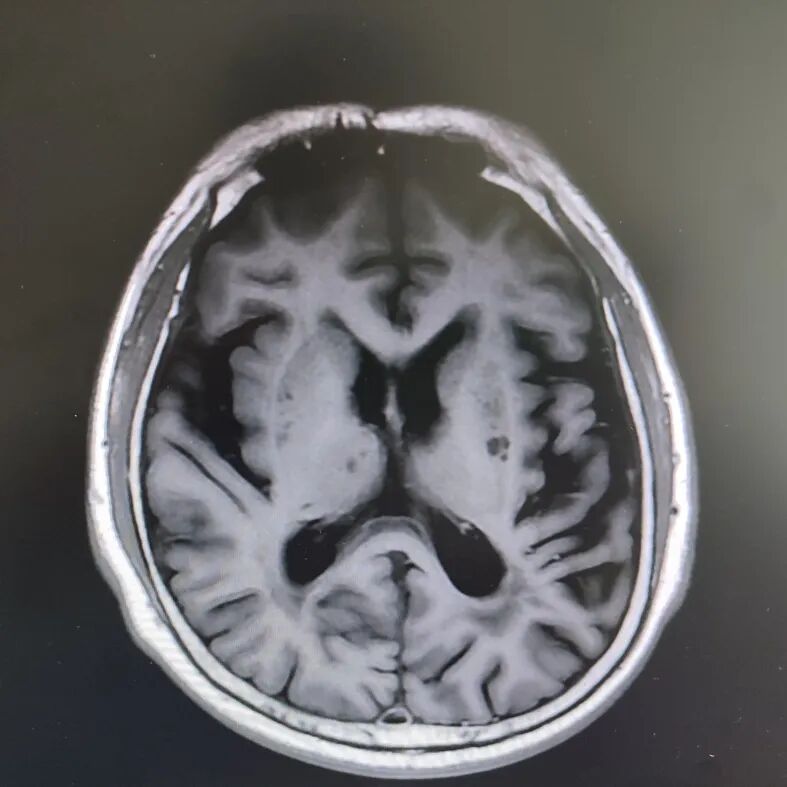

患者頭部磁共振影像